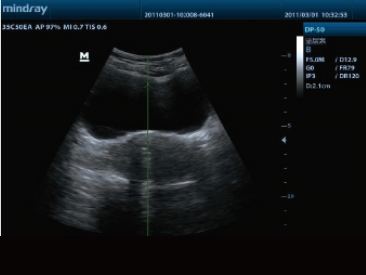

高端超声技术平台的引进,以及先进的超声成像技术的应用,给DP-50的二维图像质量带来了突破性的提升,大大的增强了超声医生的临床诊断信心。